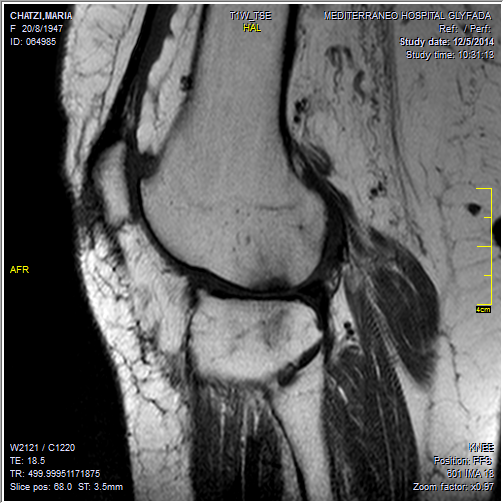

Για να πετύχει απόλυτα η έγχυση των Βλαστοκυττάρων, πρέπει η άρθρωση να προετοιμασθεί για διάστημα 6 εβδομάδων με έγχυση (μέσω ακτινοσκοπικής TV) Βιολογικών παραγόντων του αίματος, το αποκαλούμενο PRF υπό μορφή ζέλης (από το αίμα του ασθενούς).

Σχετικά με τη θεραπεία της Οστεοαρθρίτιδας του Ισχίου και των Γονάτων, το PRF χρησιμοποιείται για την αναγέννηση του χόνδρου και την ανακούφιση από τον πόνο που προκαλείται από την εκφυλιστική διαδικασία του χόνδρου στις αρθρώσεις.

Το PRF εγχύεται στην περιοχή της άρθρωσης που πάσχει, όπου οι αυξητικοί παράγοντες που περιέχονται στο πλάσμα ενισχύουν την ανάπλαση των ιστών και βοηθούν στη μείωση της φλεγμονής και του πόνου.